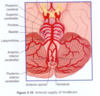

Var kommer hjärnans främre försörjningen från?

Den främre försörjningen kommer från aorta -> a. brachiocephalicus till carotis communis dx på höger sida, a. carotis communis sin på vänster sida.

Carotis communis kommer dela sig till carotis externa, som går till ansiktet, och carotis interna, som går till hjärnan.

Var kommer hjärnans bakre försörjningen från?

Den bakre försörjningen kommer från a. subclavia -> a. vetebralis som går mellan foramen transversum av C6 -> C1.

Kommer sedan gå bakom axioatlantoleden genom foramen magnum där dom 2 kollateralerna går ihop till a. basilaris.

Hur kopplas den främre och bakre arteriella försörjningen ihop?

Den främre och bakre försörjningen förbinds i cikulus wilisi. Detta sker genom 2 kommunikanter:

- Communicant anterior mellan dom 2 kollaterala ACA

- Communicant posterior mellan carotis interna och cerebri posterior.